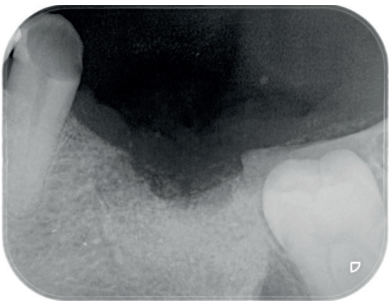

Al quinto mes se realizó un CBCT de control, para evaluar la homogeneidad en la zona y se planificó la colocación de un implante corto de 5 x 6 mm de Proclinic® (Figura 9) al mismo tiempo que fue tomada una biopsia de la zona. Se procedió a inyectar la misma anestesia que en la primera cirugía, se elevó un colgajo a espesor total y se tomó una biopsia con trefina de 3.5 mm de la zona injertada (Figura 10). En la misma zona donde fue realizada la toma de biopsia, sin pasar ninguna otra fresa, se colocó el implante empleándolo como expansor, de modo que se condensasen las paredes que rodeaban al implante (Figura 11).